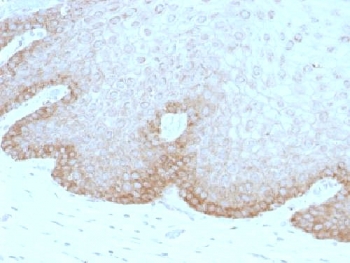

IHC testing of human cervical carcinoma with FAT2 antibody (clone 8C5). Required HIER: boil tissue sections in 10mM citrate buffer, pH 6, for 10-20 min followed by cooling at RT for 20 min.